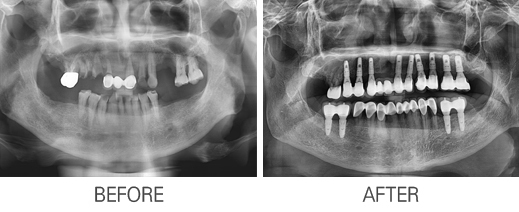

Ä«Å×°í¸®

: Àüü ÀÓÇöõÆ®

Àüü ÀÓÇöõÆ®